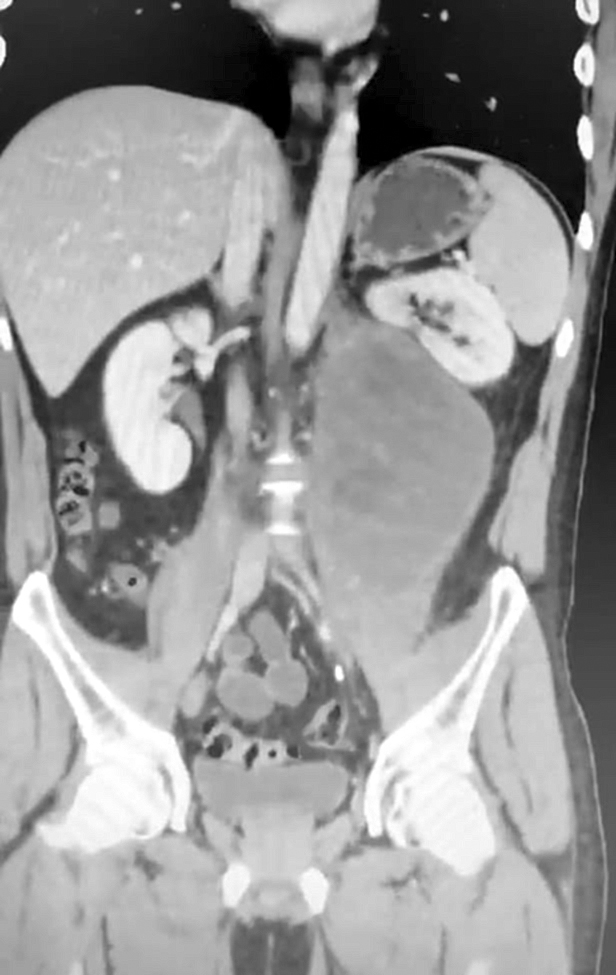

El servicio de Urología del Hospital de Especialidades Quirúrgicas IPS Ingavi realizó hoy una exitosa cirugía a un paciente de 37 años con diagnóstico de cáncer de testículo izquierdo en estadio 3. Tras cuatro sesiones de quimioterapia, el paciente presentaba una formación tumoral voluminosa en retroperitoneo izquierdo, de aproximadamente 20 cm de diámetro, que provocaba dolor lumbar y trastornos intestinales.